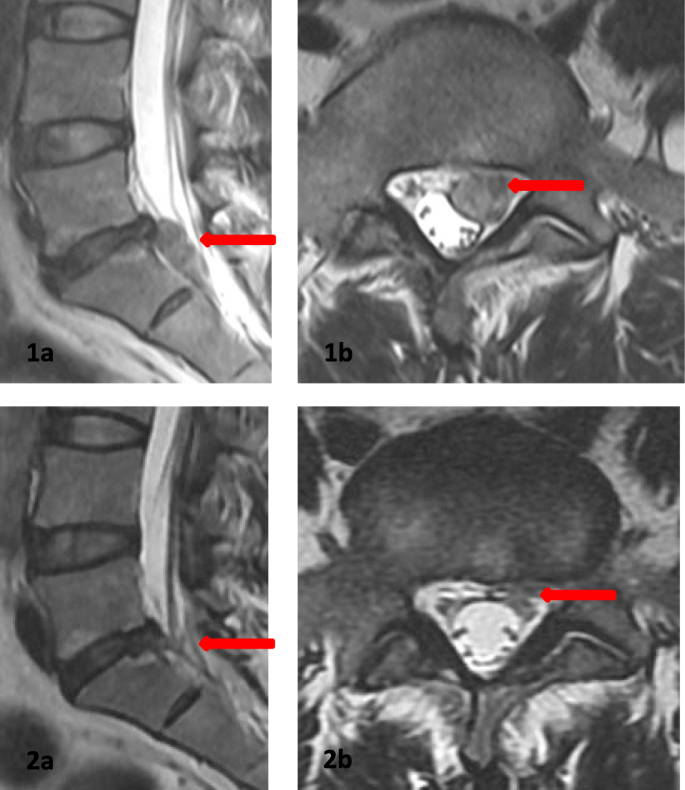

intervertebral disc herniation